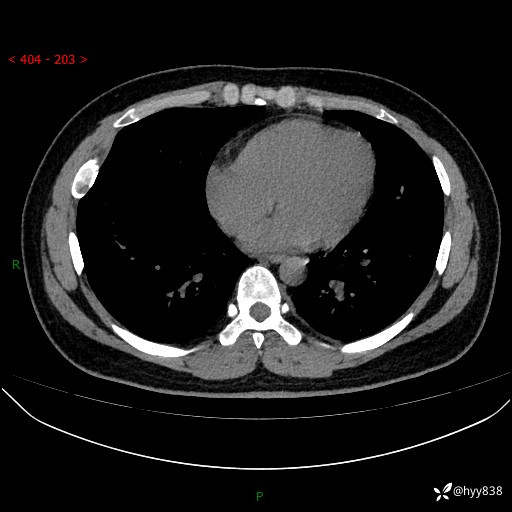

年轻小伙,右侧胸部疼痛4天余。病理科说肯定不是骨纤,那是啥---结果公布~

年龄:24岁

主诉:右侧胸部疼痛4天余。

现病史:患者约4天前突发右侧胸部疼痛,无瘙痒,无头痛、头晕,无心慌、胸闷、呼吸困难、咳嗽、咳痰、咯血,无腹痛、腹胀等不适,未作进一步诊治。于2024年5月外院行胸部CT平扫示右侧肋骨骨质改变。现为求进一步治疗,遂于我院就诊。门诊以“胸壁肿物”收入我科。 患者自起病以来,精神可,睡眠可,饮食可,大小便正常,体重无明显改变。

胸部CT平扫